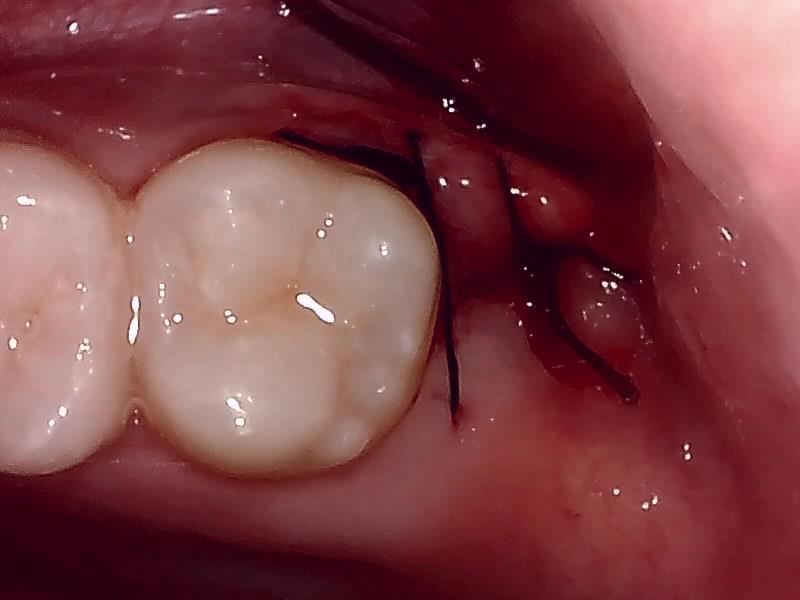

縫合 (左上)

当院では、傷口は最小限に、骨は極力削らずに行います。

骨が歯を覆っているケース以外は骨を削ることはありません。

親知らずのみにアプローチし歯を分割し最小限の傷口で取り出します。

歯肉を切開し、歯が見えるようにして、

周辺の骨を削らないように親知らずを分割し抜きやすくしていきます。

この抜歯法により術後の腫れ痛みが大幅に軽減されます。